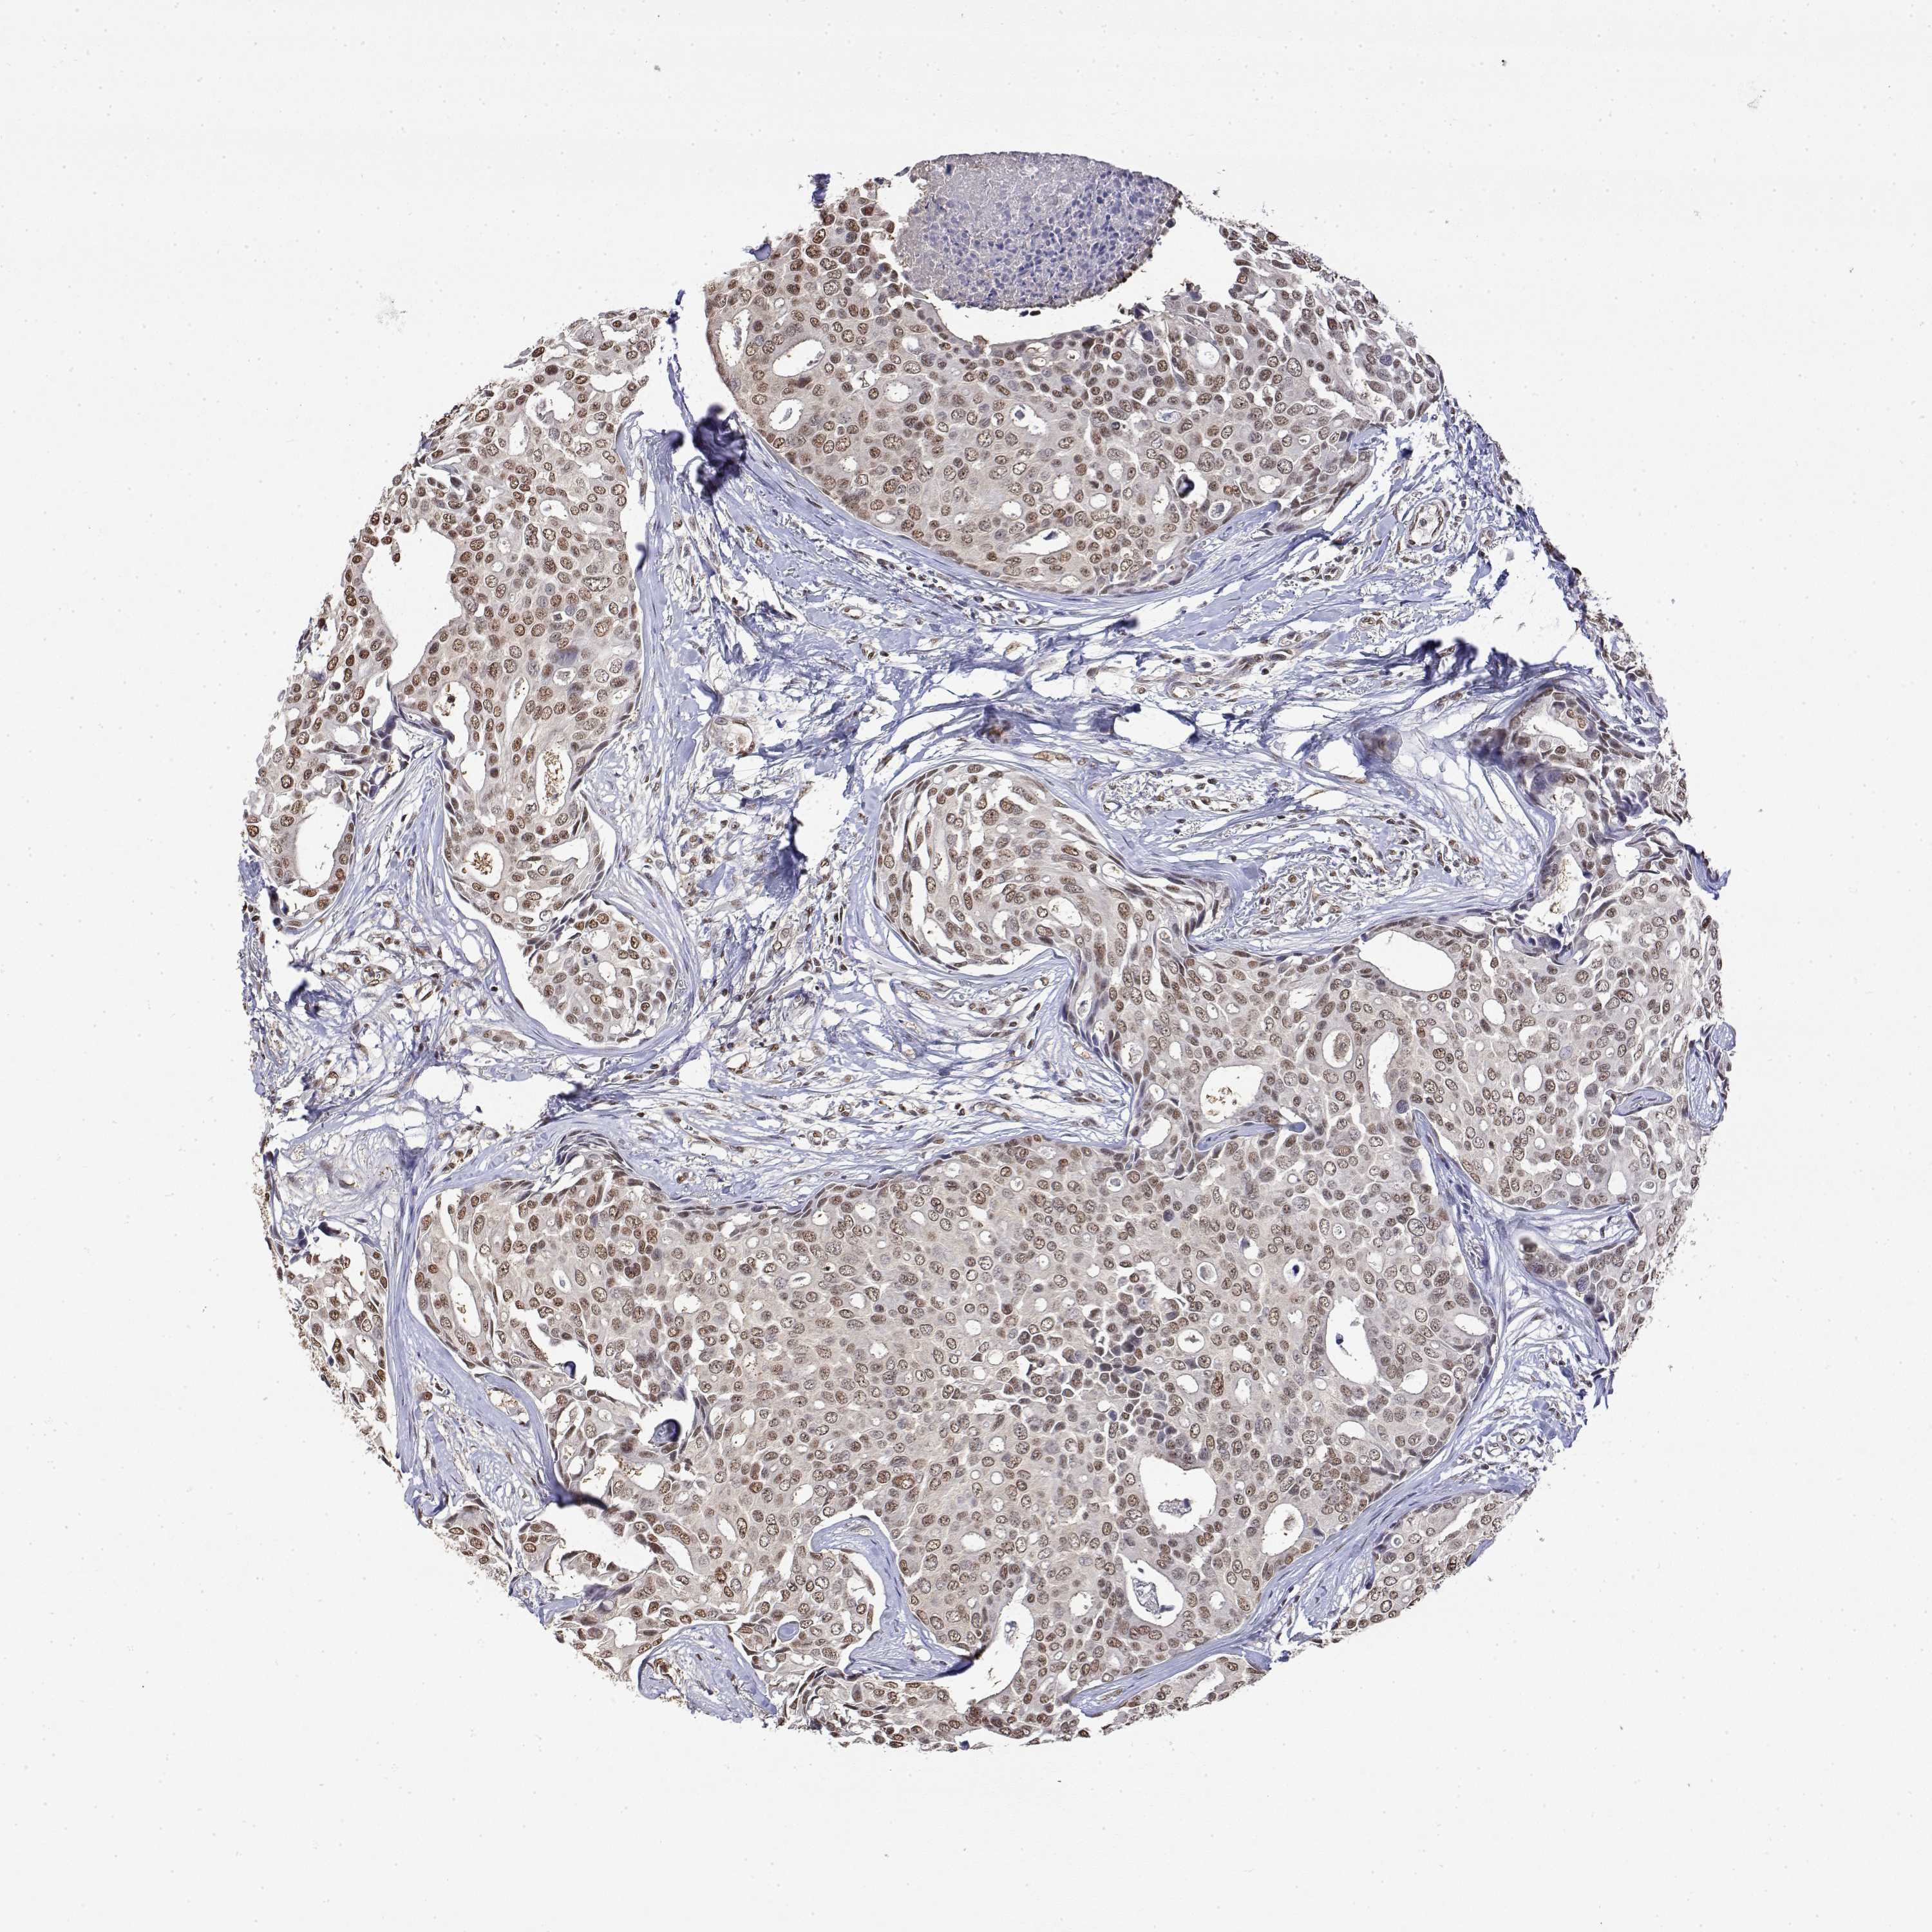

BRCA TCGA BRCA VALIDATION PROTEIN EXPRESSION